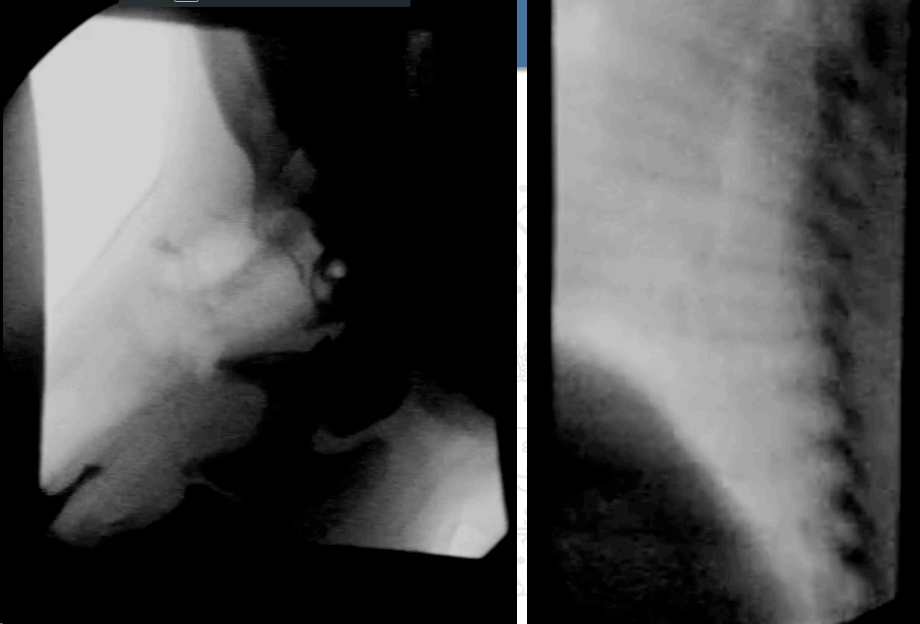

El revelado de la placa puede ser manual o automático con reveladora, para la visualización se usa un negatoscopio. Para intensificar la imagen se usan pantallas fluorescentes; esto reduce la dosis absorbida, pero reduce la resolución y aumenta el ruido. Sirve para estudios en movimiento, imágenes de menor tamaño e invertidas. Se usa sistema de telefisión.

Los arcos de fluoroscopia de componen de: